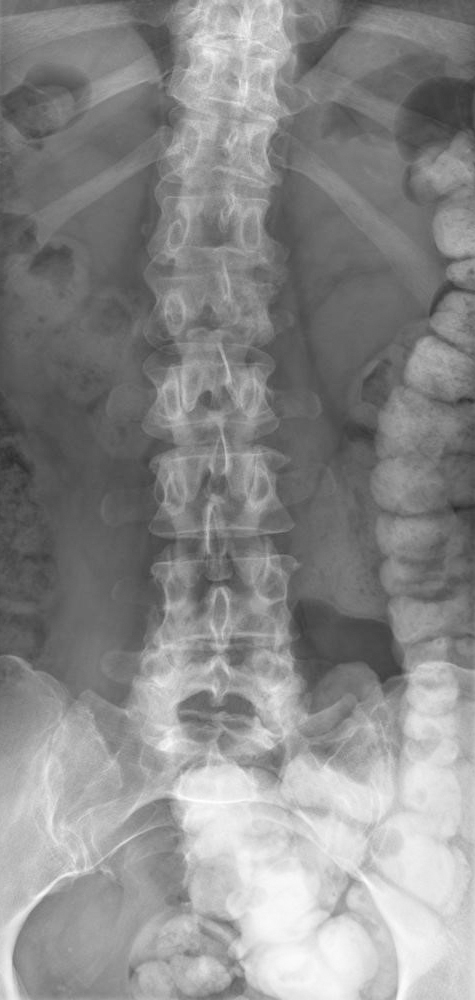

La patiente bénéficie d’une radiothérapie mammaire adjuvante, sans radiothérapie ganglionnaire. Il est prévu une hormonothérapie pendant cinq ans, qui est débutée par du tamoxifène, avant d’être relayée par du létrozole (inhibiteur de l’aromatase) à ses 49 ans, en raison de sa ménopause. En raison des arthralgies causées par les inhibiteurs de l’aromatase, ceux-ci doivent être arrêtés précocement, après quatre ans de traitement au total. Vous réalisez un suivi conjoint entre chirurgien et oncologue médical, puis, après dix ans, la patiente est perdue de vue. Elle vous reconsulte alors qu’elle a 61 ans. Depuis, elle est suivie pour une hypertension artérielle, traitée par amlodipine. Elle est toujours fumeuse à 25 PA. Elle vous décrit des douleurs rachidiennes d’horaire inflammatoire durant depuis deux mois environ, associées à une légère anorexie, lui ayant fait perdre 4 kg en un mois (elle pèse maintenant 71 kg). Il n’existe pas de composante neuropathique à sa douleur, et pas de déficit sensitivo-moteur. Les réflexes ostéo-tendineux sont normaux. Son médecin traitant lui a prescrit de faibles doses de morphine, ce qui la soulage, et a fait réaliser l’élément suivant :

Question 11 - Concernant le tableau présenté par la patiente :

Il s’agit d’un effet indésirable connu des inhibiteurs de l’aromatase, mais la perte du pédicule latéral gauche de L2 (vertèbre borgne) est en faveur d’une récidive.

L’aspect de vertèbre borgne est hautement évocateur d’une récidive (envahissement du pédicule latéral).

Nécessaire afin de préciser des lésions rachidiennes et le risque neurologique, discuter une prise en charge chirurgicale…

Vous organisez en effet un TEP-scan afin de réaliser un nouveau bilan d’extension devant cette probable récidive. Toutefois, le suivi d’un cancer du sein repose uniquement sur la mammographie +/- échographie et l’examen clinique.

L’introduction d’un traitement par bisphosphonates se discutera ici après un bilan global, dans le cadre d’une possible maladie osseuse généralisée.

L’aspect de vertèbre borgne est fortement évocateur d’une récidive tumorale. On doit compléter le bilan par une IRM afin de préciser les lésions rachidiennes, préciser le risque neurologique et discuter d’un geste à visée antalgique (chirurgie, radiothérapie, cimentoplastie…). On doit également réaliser un bilan d’extension (TEP-scan ou scintigraphie osseuse et scanner thoraco-abdomino-pelvien [TAP]), afin de préciser l’étendue d’une probable récidive, et préciser la lésion à biopsier.